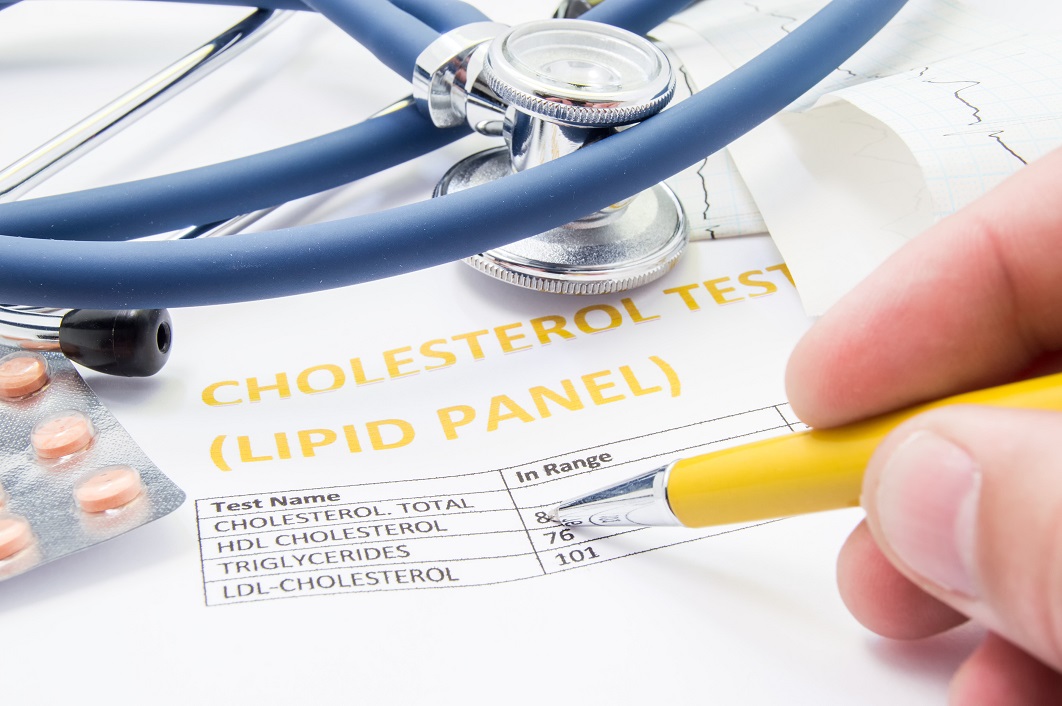

Experts are now suggesting a more tailored approach for men and women with high blood pressure due to a difference in dementia risk. In a new study from George Institute, researchers found that a link between mid-life cardiovascular events and dementia was similar in both men and women. But for blood pressure, the results were ...click here to read more